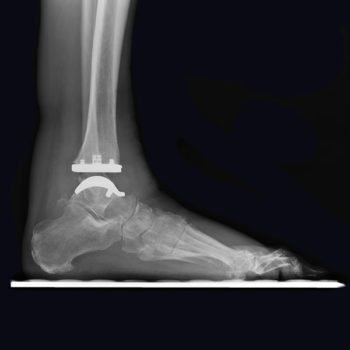

Basierend auf einer firmeneigenen CT-Rekonstruktions-studie wurde die tibiale Komponente so gestaltet, dass eine anatomische kortikale Abdeckung gewährleistet und die fibulare Artikulation ungehindert möglich ist.1,2 Während sich die kurvierte Talus-Komponente der trabekulären Knochenstruktur des Talus anpasst, um inhärente Stabilität zu erreichen, wird die primäre Stabilität bei der flach geschnittenen Talus-Komponente durch einen Press Fit Hohlzapfen und die peripheren Plasmazapfen gewährleistet.

Der Radius der Krümmung auf der Unterseite der Talarkomponente basiert auf Studien, die die Wirkung der Arthrose auf den Talus untersuchten. Das spezifische Design entspricht der krankheitsbedingten Oberflächenveränderung und kann so die erforderliche Menge an Talarresektion reduzieren.2